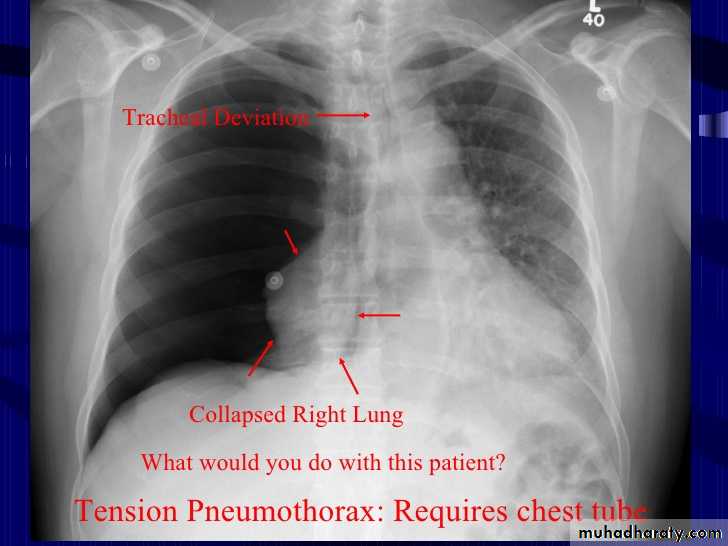

Tension pneumothorax

56.tension pneumothorax left sided aspect

57. tension pneumothorax right sided aspect